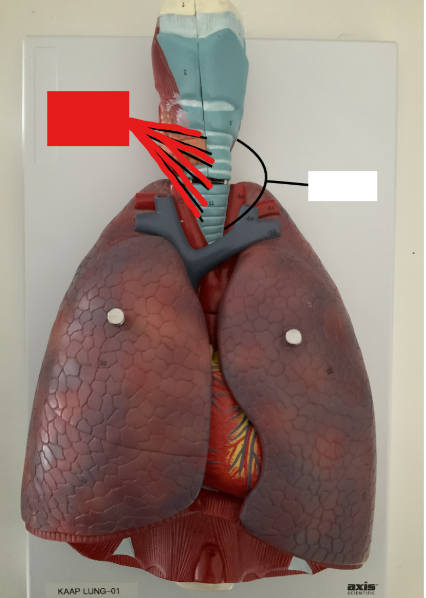

What structure is this?

Trachea

What structure is this?

Tracheal Cartilage

What structure is this?

The carina